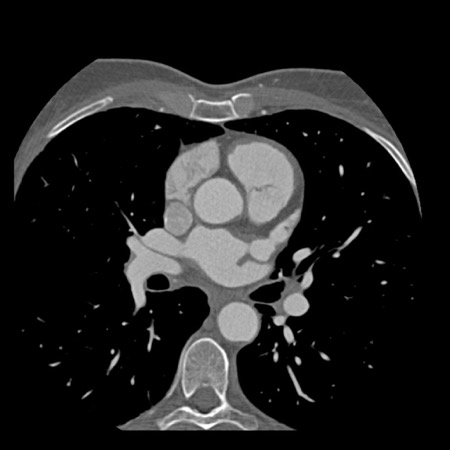

case 3 – Calcium score 0 and severe stenoses.

First, scroll through the CTA images.

How would you describe the findings on the coronary CTA?

The findings are:

- The total calcium

score of 0 indicates the absence of calcified plaque in the coronary

tree. - Severe stenosis

(70-99%) in the mid LAD and D2 branch.